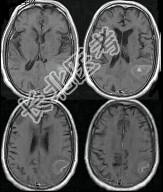

- 单项选择题男,76岁, 突发神志不清,伴呕吐6小时, MRI检查如图所示,最可能的诊断为 ( )

A、出血性脑梗死

B、肿瘤出血

C、原发脑出血

D、脑结核

E、脑脓肿